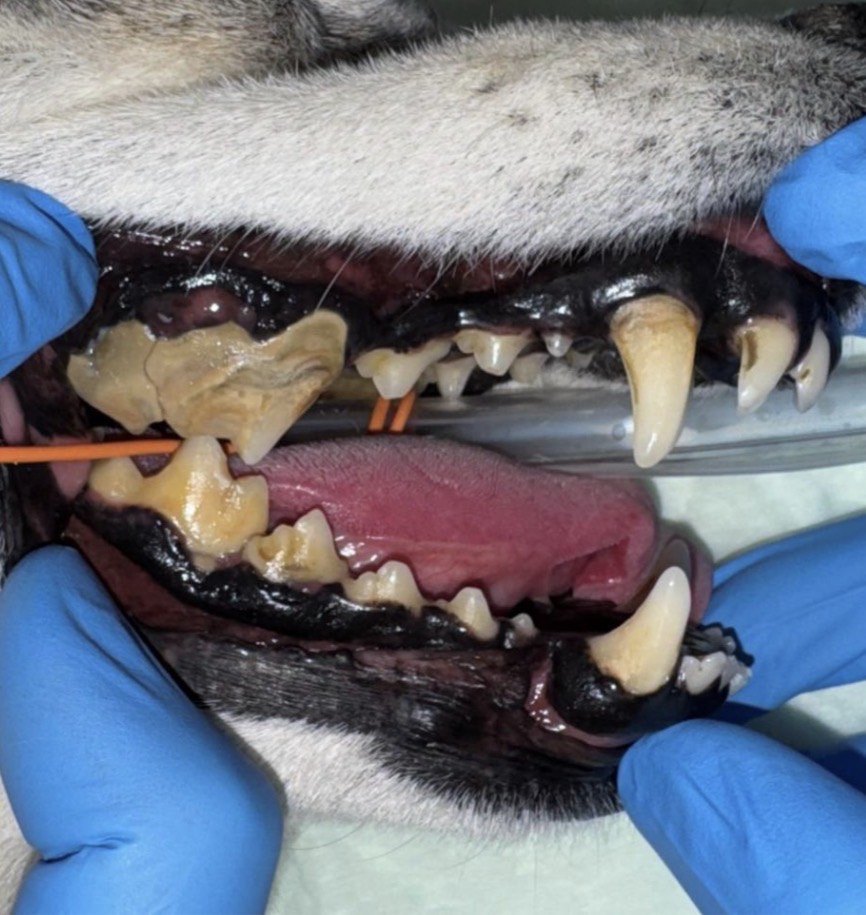

今回は歯磨きを頑張っていたけれど、歯を痛がる様子が見られた柴犬さんをご紹介させていただきます。

• 犬種 柴犬

• 年齢 12歳

• 性別 避妊雌

• 症状 歯を痛がる

• 病名 重度歯周炎、破折、露髄

• 処置 歯石除去、抜歯

全身麻酔下で、口腔内の評価と歯科レントゲン撮影を行ったところ、重度の歯周炎・破折・露髄(神経や血管などが通っている組織が露出)が確認されました。

また、左上顎第4前臼歯・右上顎第4前臼歯・右上顎第2切歯に重度の動揺が確認されました。

左上顎第4前臼歯では歯根破折、左上顎第2切歯では破折(露髄)が認められました。